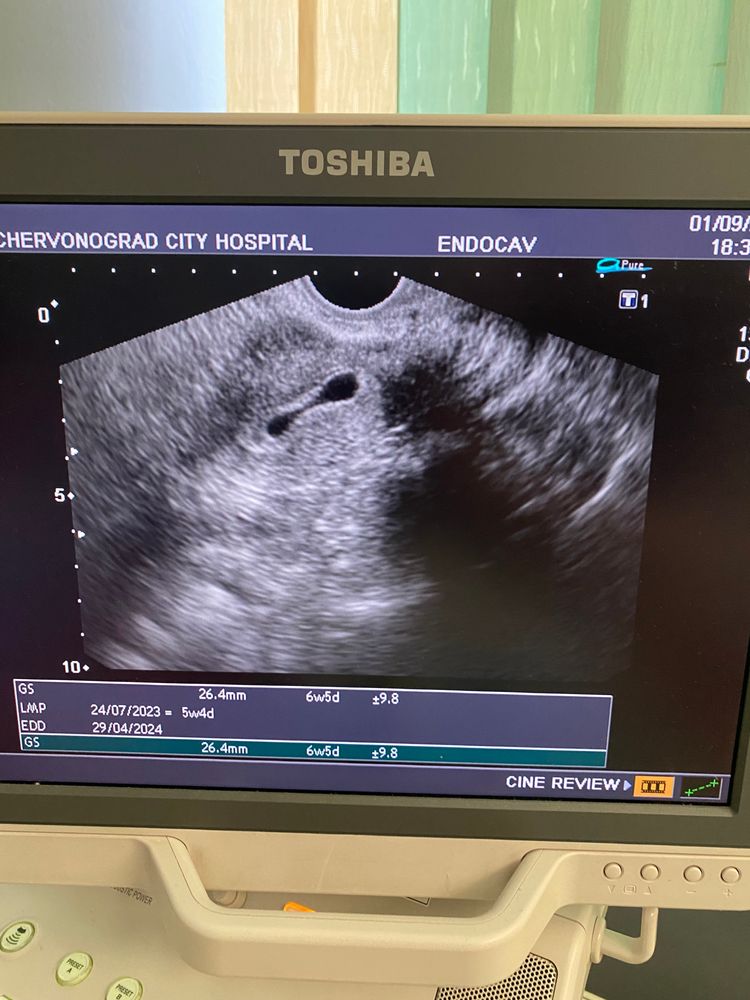

Вот и закончились дни моего счастья. Сегодня 21дпп, сделала такой красивый тест на память утром, а после обеда кровотечение и конец… Плодное яйцо еще было, на деформировано и после кровоостанавливающей капельницы, все вышло. Я впервые видела как мой муж рыдал… и пустота